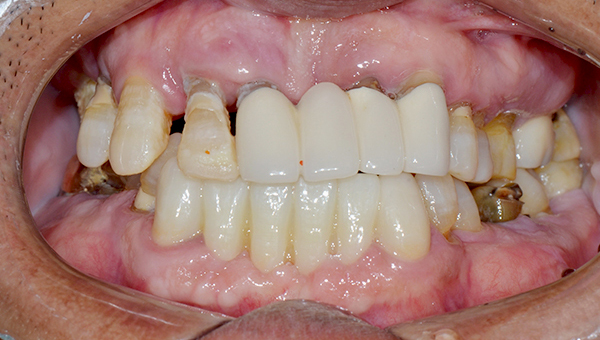

안*명 임플란트 시술 사례

상악 전체/ 하악 구치부 임플란트

2024.10.11

치료 전

2025.04.14

치료 후